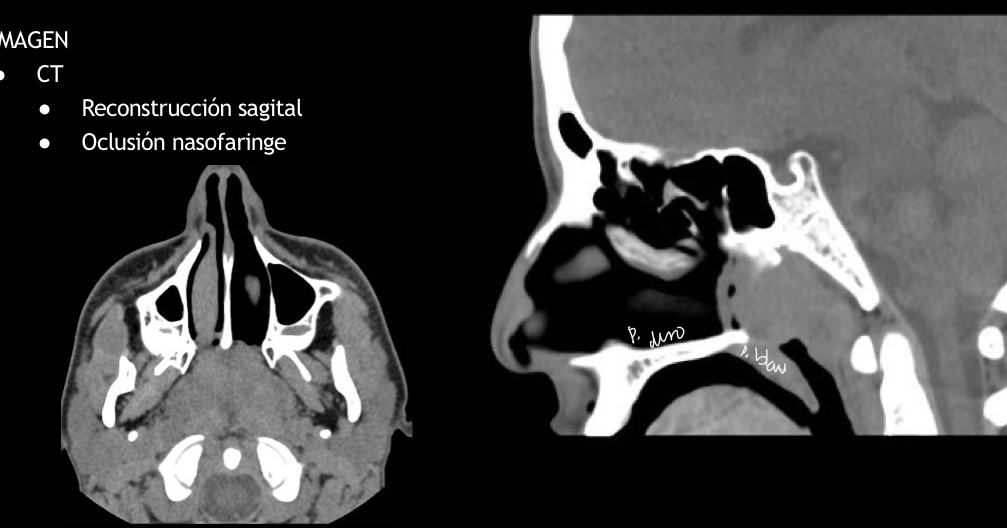

Q se ve en tc

oclusion nasofaringe

Hay reconstruccion sagital